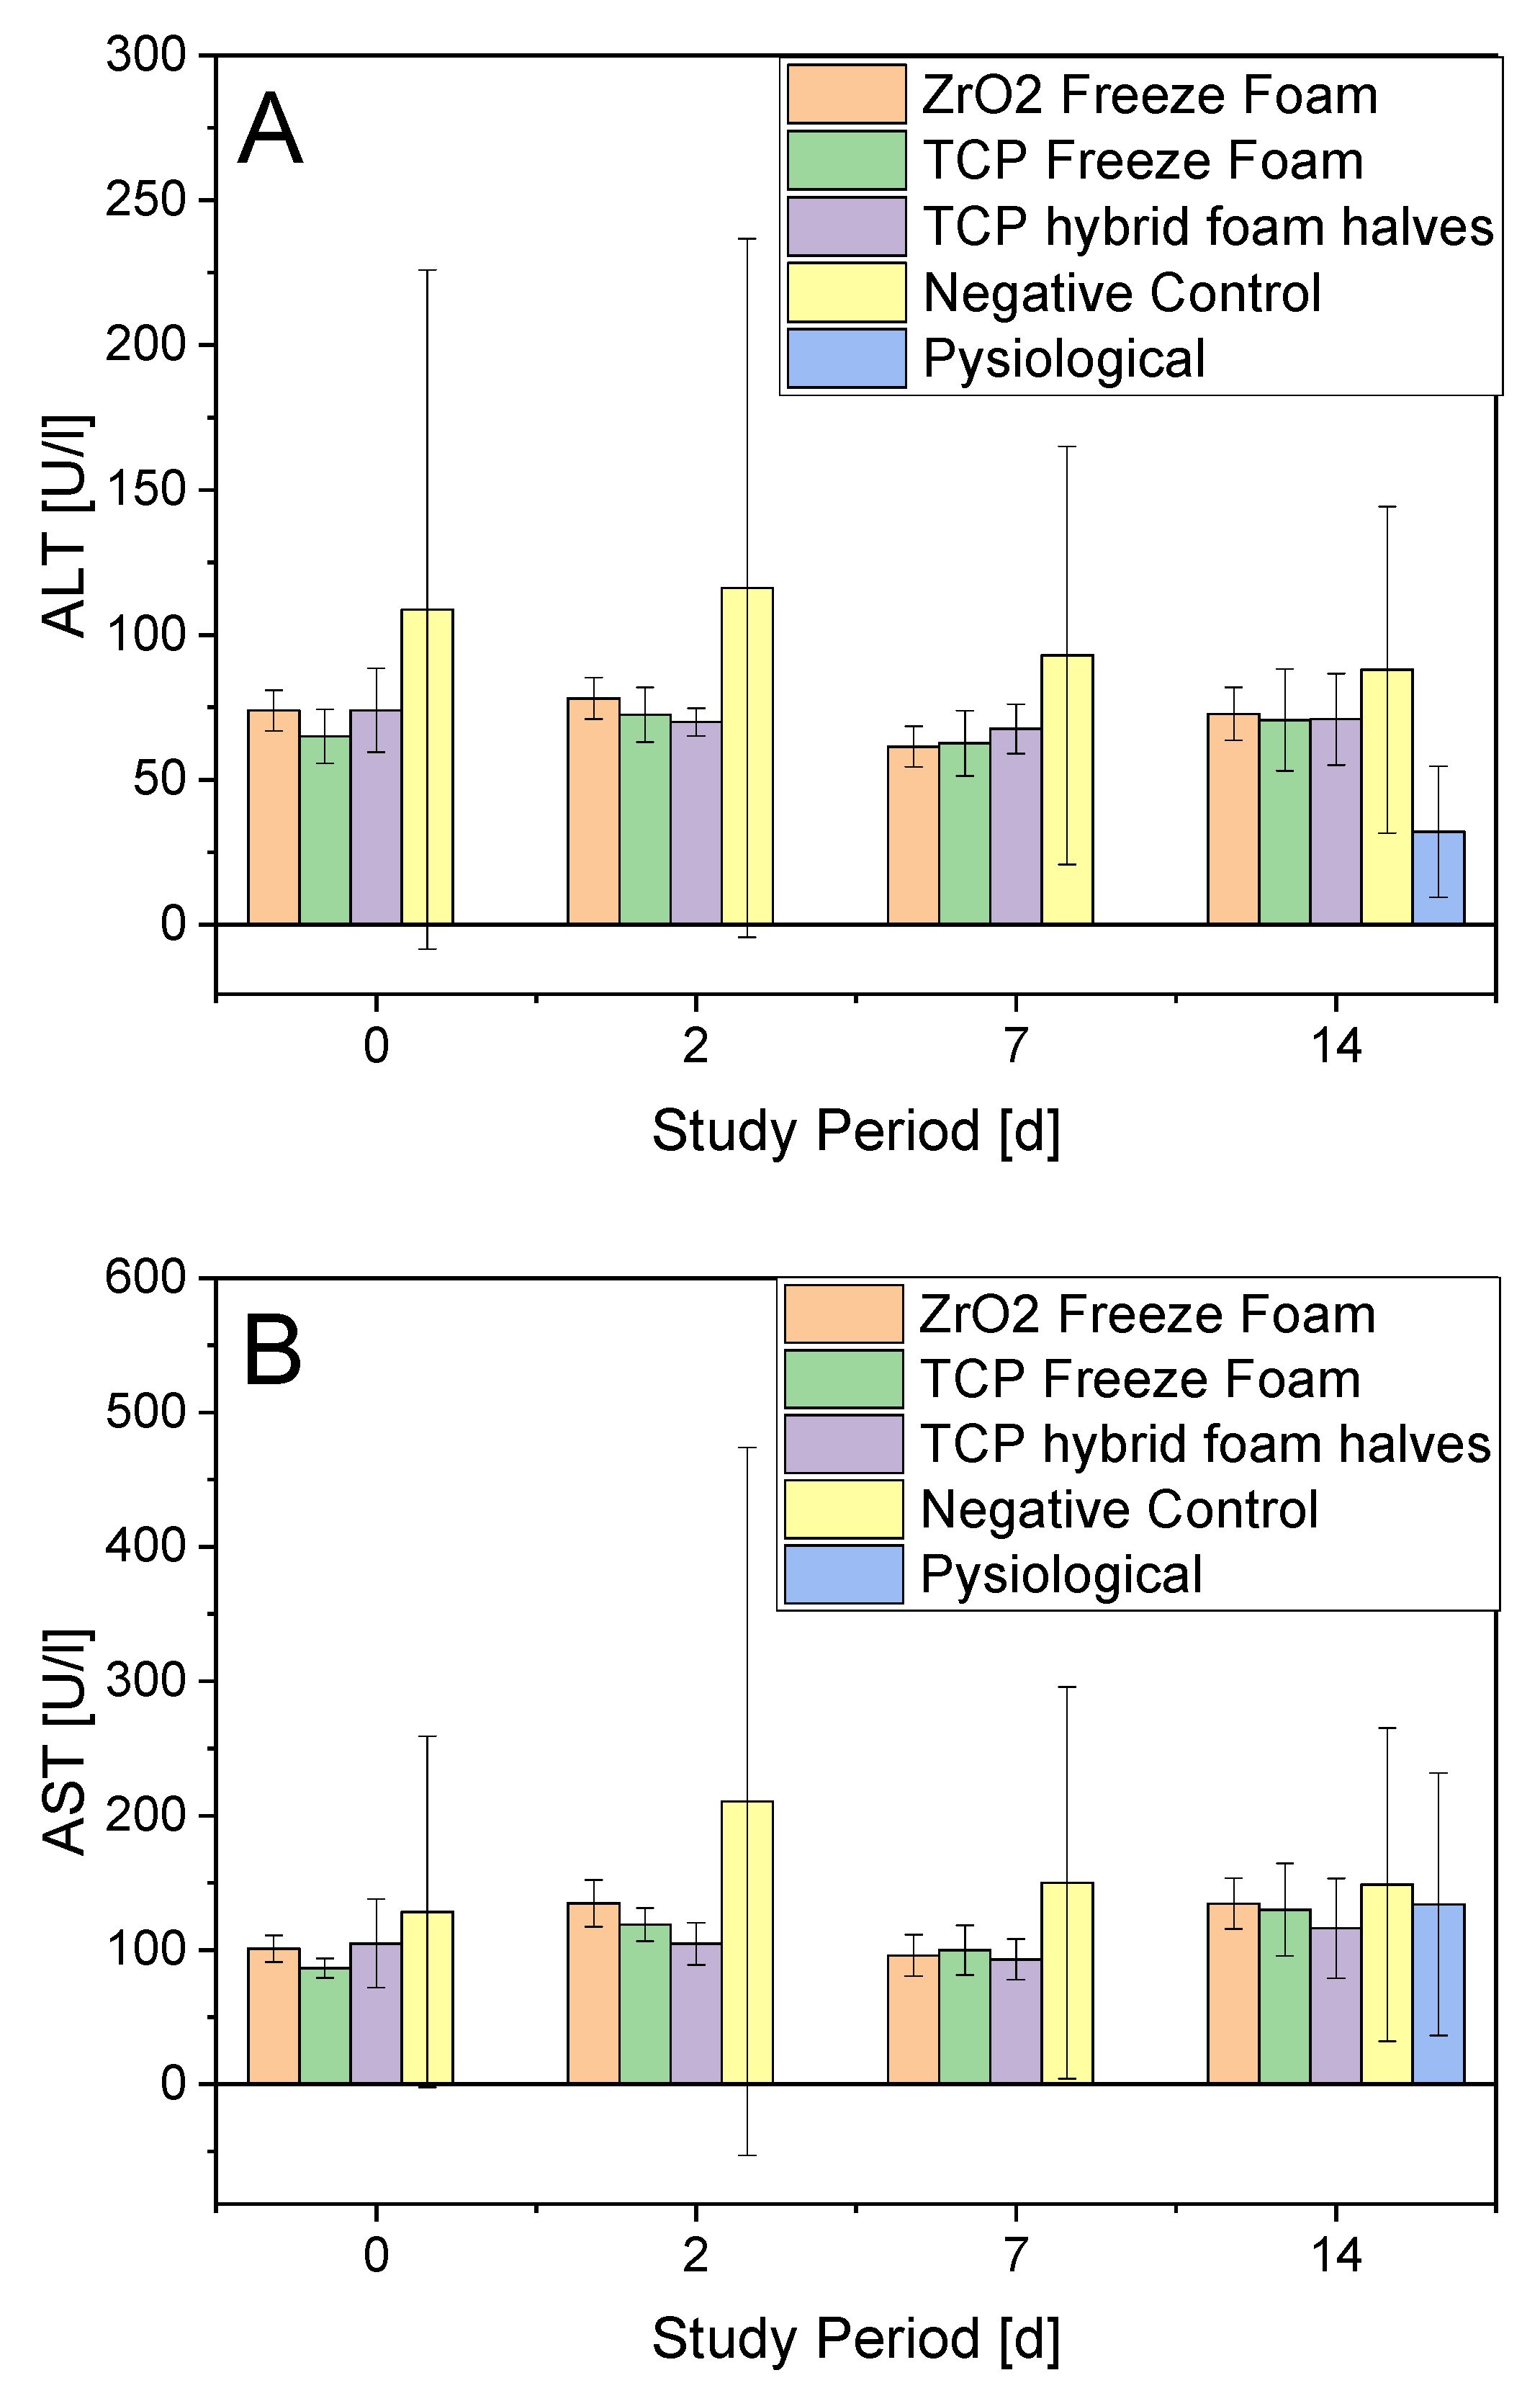

3.4. In Vivo Studies

- Serum Parameters

3.4.1. ALT

3.4.5. In Vivo Conclusion

4.2. Biocompatibility

5. Conclusions